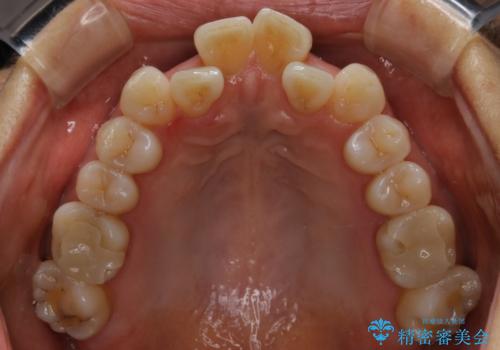

前歯の反対咬合、奥に引っ込んでしまっている歯をインビザラインで治療する

- インビザラインでの治療を希望した患者様です。

上の前歯の反対咬合があり、治療の途中で下の前歯を乗り越える必要があります。